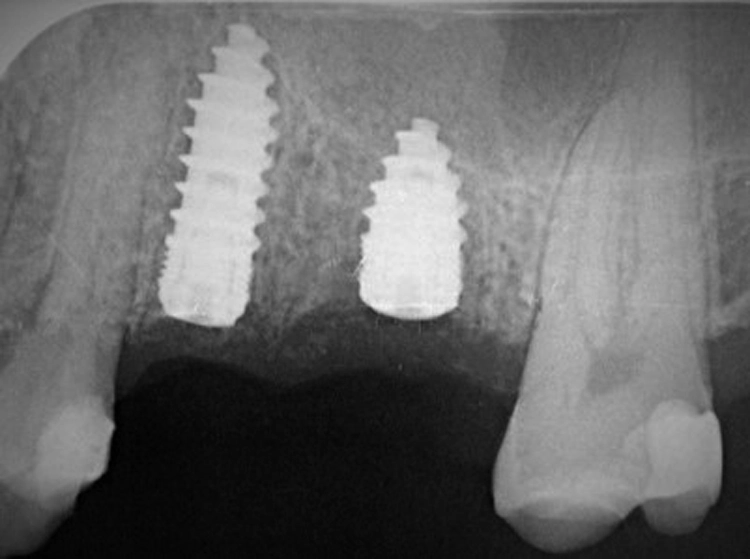

Nach der Pilotbohrung wird das Implantatbett mit Condensern in aufsteigenden Durchmessern aufbereitet. Erreicht man mit einem Condenser „handfest“ eine Stabilität von 20 Ncm, so wird ein Implantat mit dem nächstgrößeren Durchmesser inseriert. Die Bilder (Abbildungen 4a-h) zeigen das Beispiel einer Sofortimplantation regio 16.

Dr. Volker Knorr, Eislingen

Es wurde ein Champions (R)Evolution-Implantat ø 4,5 mm – L 8 mm in Verbindung mit einem internen, direkten Sinuslift (IDS) inseriert. Mit dem Condenser ø 3,8 mm wurden „handfest“ (etwa 20 Ncm) erreicht und deshalb ein Implantat ø 4,0 mm inseriert. Hätte man die Stabilität erst mit dem Condenser ø 5,3 mm erreicht, so hätte man ein Champions (R)Evolution-Implantat gleicher Länge, aber mit dem Durchmesser 5,5 mm einsetzen sollen.